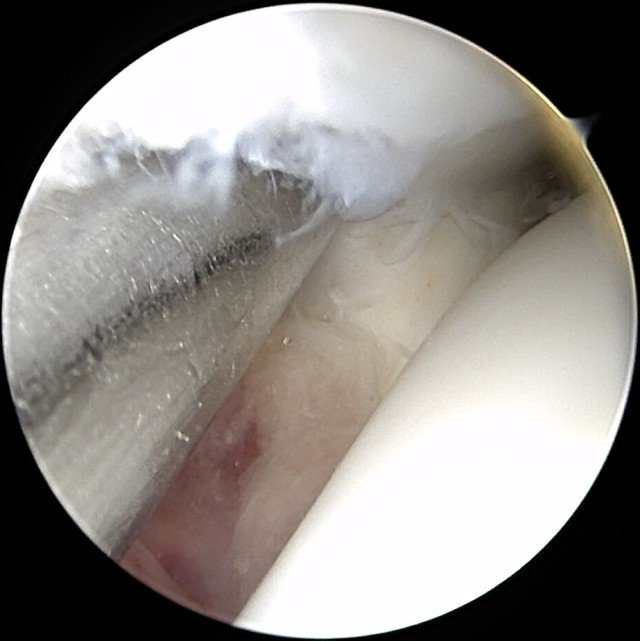

Unstable injuries treated within six weeks of injury require "keyhole surgery"

involving ankle arthroscopy and syndesmotic stabilisation using one or two TightRope or ZipTight

devices (see images below).